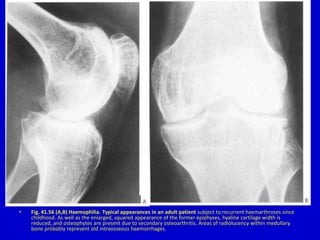

• Fig. 41.56 (A,B) Haemophilia. Typical appearances in an adult patient subject to recurrent haemarthroses since

childhood. As well as the enlarged, squared appearance of the former epiphyses, hyaline cartilage width is

reduced, and osteophytes are present due to secondary osteoarthritis. Areas of radiolucency within medullary

bone probably represent old intraosseous haemorrhages.